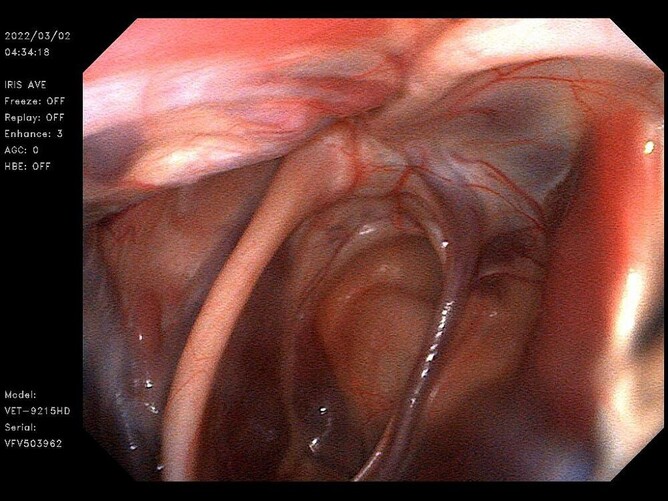

We are able to utilise this fantastic piece of equipment to view the upper and lower respiratory tract of horses with the 1.5m endoscope able to view the bifurcation of the lungs. Imaging the guttural pouches and upper airways is now much more rewarding when everyone can see what is going on. This piece of equipment also allows us to guide treatment in a much more user friendly and accurate manner. The 1.5m scope can also be used to look into the bladder and the uterus and has been used by the small animal team to look into large dogs stomachs and view the upper small interesting.

Check out some of our captures:

Lower Air Way Video Endoscope